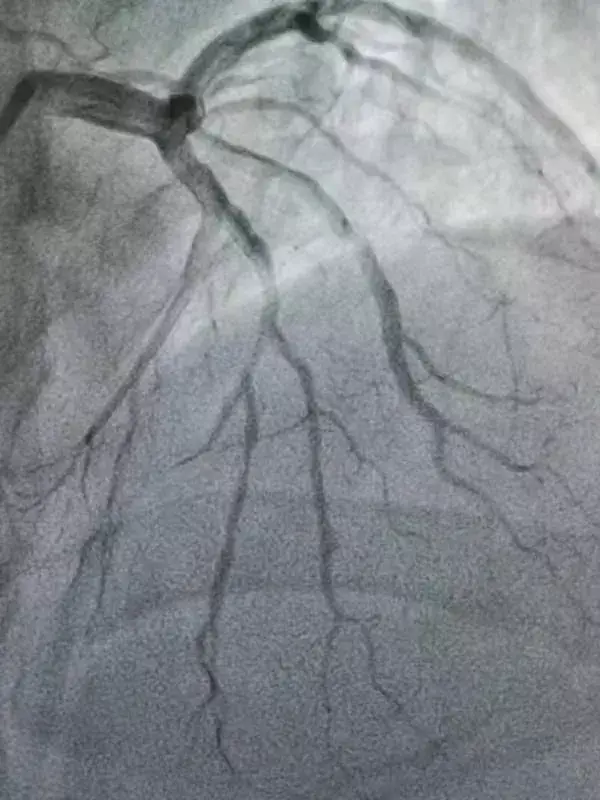

术后

术后患者症状缓解,并对王昌育主任及心内一手术团队表示真挚的感谢。王昌育主任医师缓缓的对患者说:“疫情无情人有情,我不仅要对你们患者负责,也要对我们医护人员负责,也是我院各科室、部门相互协作才能顺利给您完成手术,祝您早日康复!”说完便转身离去,只留下坚毅的背影和湿透了的手术衣。